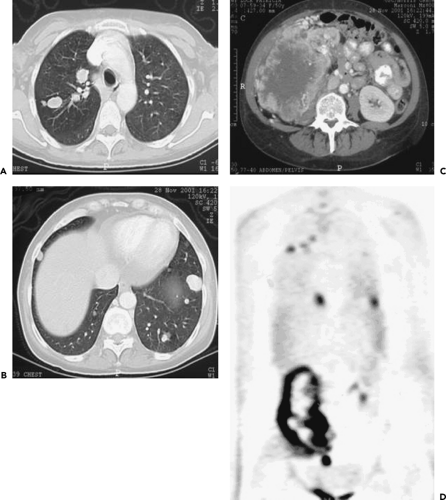

![[ 18 F]Fluciclatide PET/CT images of a right kidney tumor (arrows) in ...](https://www.researchgate.net/publication/263475425/figure/fig3/AS:512809851158528@1499274804097/18-FFluciclatide-PET-CT-images-of-a-right-kidney-tumor-arrows-in-patient-10-Axial.png)